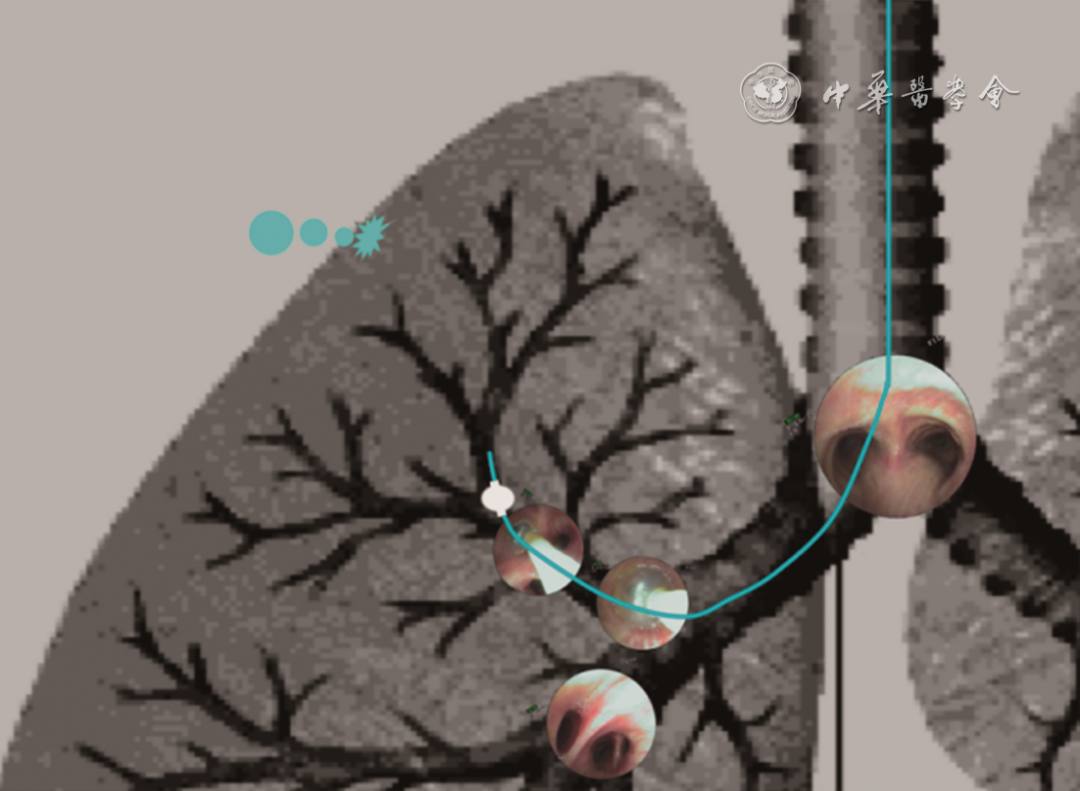

1. 球囊探查定位责任引流支气管(图1):(1)基本原理:球囊探查的原理是通过球囊填塞阻断责任引流支气管的气流,从而使胸膜瘘口停止漏气。球囊探查由于其简便、有效、经济及安全等优点广泛应用于临床,即便在机械通气情况下也可安全地使用小球囊进行责任引流支气管探查。目前国内外的文献中关于难治性气胸病例数较大、资料较全面的临床研究包括我国、日本以及美国 3项临床观察,均采用球囊探查的方法来对责任引流支气管进行定位。(2)技术流程:经支气管镜工作通道送入球囊导管,将球囊导管送达不同叶段支气管开口,充盈球囊使之紧密堵塞支气管开口,观察水封瓶中气泡是否明显减少或完全停止,若明显减少或完全停止说明该支气管为胸膜瘘口所属肺叶肺段的责任引流支气管。探查步骤如下:①根据术前影像资料可先对可疑支气管进行探查;②对无任何线索者按照“上叶~下叶~中叶支气管”的顺序进行探查;③“先叶后段”探查,多数情况下不需探查到亚段。向亚段或更远端支气管进行探查将大幅度增加操作时间并降低患者的耐受性,且多数情况下亚段之间存在侧支通气,探查不易成功;④以水封瓶中气泡明显减少或完全停止为标准确定责任引流支气管,临床上通常采用肉眼判断水封瓶的气泡量。近期,美国食品及药物管理局(food and drug administration,FDA)已经批准使用数字化胸腔引流系统,如Thopaz(瑞士Medela公司),可对胸腔气体引流量及压力进行数字化监测。如将球囊探查与数字化胸腔引流监测系统结合,则可更加客观地判断探查的结果;⑤建议对探查结果阳性的责任引流支气管进行3次验证;⑥不少患者存在跨叶段或多叶段的胸膜瘘口,用球囊单独探查一个叶段无法使引流管气泡停止、使定位困难,这时可在段以上的支气管进行探查,然后再分别对其所属的各个段进行封堵。(3)评价:球囊探查的阳性率为64.3%~85.0%,失败的主要原因包括两方面,其一是不同肺叶肺段之间存在侧支通气,其二是存在多叶段瘘口。其他原因还可能包括技术细节上的掌握,如球囊的充盈程度(贴壁性)是否足以阻断该支支气管的气流。

7b4d689e4de9733672033166356b50c8.png

图1 球囊探查法示意图